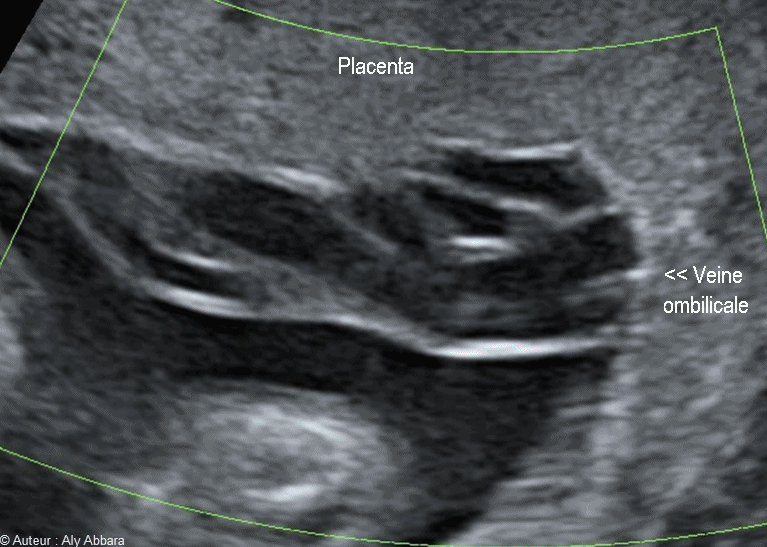

Le flux sanguin dans la veine ombilicale naissant du bord du placenta - الدوران الدموي داخل الوريد السري إبتدأً من منشأه من المشيمة

• Vidéo échographique montrant le flux sanguin (en Doppler type Dynamic-Flow et écho 2D) dans la veine ombilicale au niveau de sa naissance sur le bord du placenta.

• La direction du flux sanguin dans la veine ombilicale : placenta > foetus

• Grossesse de 33,5 SA